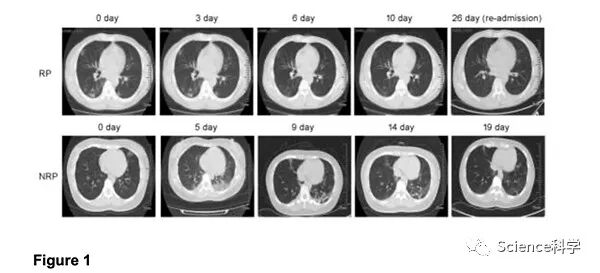

通过回顾发现,与非复阳患者相比,复阳患者在住院期间表现出更少的症状,更持久的CT成像缓解和更早的RNA转阴,但血浆抗体水平表现与非复阳患者相似。重新入院后,这些复阳患者没有表现出明显的临床症状或疾病进展,CT影像正常以及炎症性细胞因子水平也正常。复阳患者的所有21位密切接触者的核酸检测均为阴性,并且未报告可疑的临床症状。

值得注意的是,与轻度非复阳患者相比,轻度复阳患者的最初症状较轻(p <0.01)。同时,轻度复阳患者中有45.5%在首次入院时仅表现出上呼吸道症状,而轻度非复阳患者通常在初次入院时表现出下呼吸道症状。复阳和非复阳的中度分期患者在第一次胸部CT成像中病变程度没有差异。然而,与非复阳患者相比,研究发现复阳的发生率(85.2%)与胸部CT影像学的持续缓解特别相关。而非复阳患者中,36.2%在首次住院期间表现出暂时性的恶化。

所有38例复阳患者均重新入院接受进一步医学观察。分析表明,所有这些患者均未发烧。少数患者报告了轻度的咳嗽和胸闷,并没有比以前恶化。

所有轻度复阳患者均随后恢复,中度患者中37.0%的胸部CT成像正常,无炎症迹象,另外63.0%(n = 17)的胸部CT成像则显示有炎症迹象。所有复阳患者入院时淋巴细胞计数,血浆IL-6和CRP水平均在正常范围内。入院后只有1例患者接受过短暂的α干扰素吸入治疗,4例患者接受了低流量氧气吸入治疗和中药治疗。